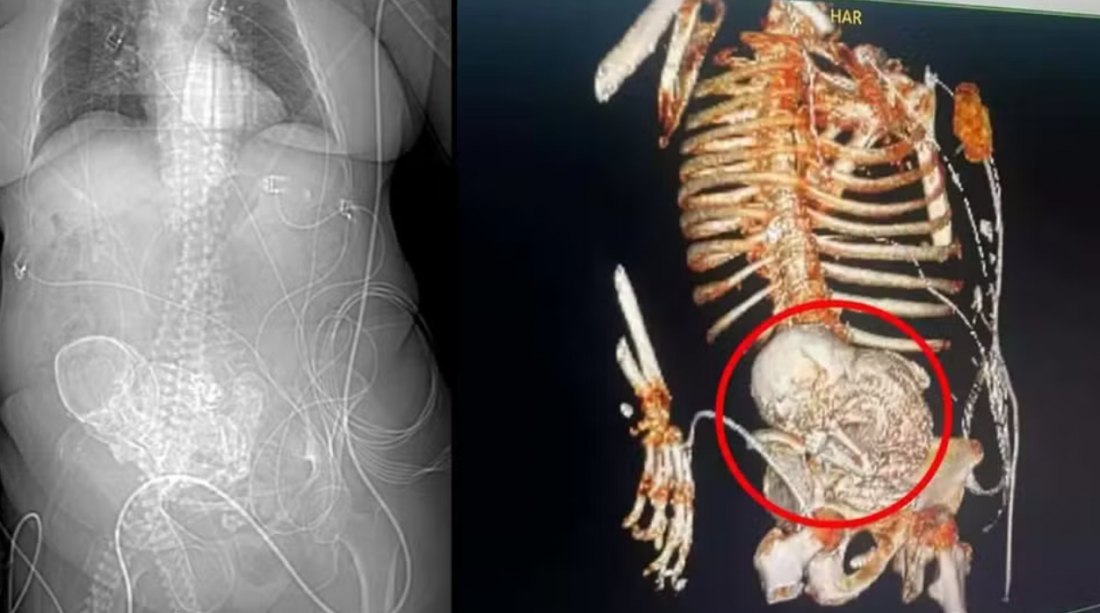

A paciente deu entrada no Hospital Regional de Ponta Porã com um quadro de infecção grave em 14 de março. No mesmo dia, uma tomografia constatou o feto calcificado na região do abdômen dela. Veja o vídeo mais acima.

Após a idosa dar entrada no HR de Ponta Porã, em 14 de março, uma tomografia 3D foi solicitada para precisar o diagnóstico. O exame que identificou o feto calcificado no abdômen da mulher, de acordo com as informações da secretaria de Saúde de Ponta Porã.